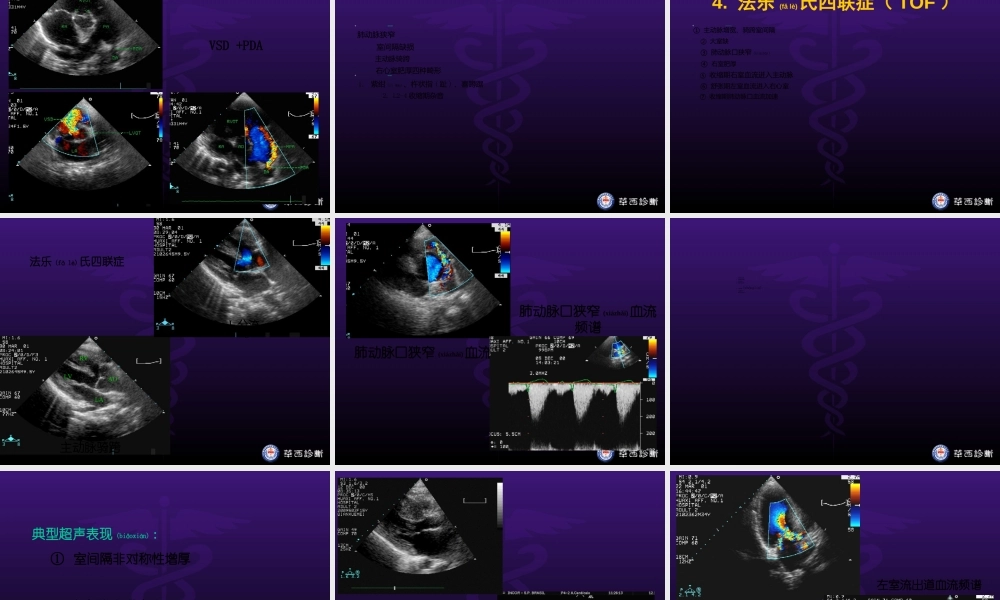

超声心动图3Echocardiography,UCG四川大学华西医院(yīyuàn)心血管内科唐红第一页,共四十四页。一、心脏解剖二、超声心动图的检查方法常规(chángguī)方法特殊检查方法三、常见心血管疾病的超声诊断(一)风湿性心脏病(二)冠心病(三)先天性心脏病(四)心肌病和其他第二页,共四十四页。(三)先天性心脏病1.房间隔缺损2.室间隔缺损3.动脉导管(dǎoguǎn)未闭4.法乐氏四联症(TOF)第三页,共四十四页。形成机理:第二房间隔发育异常或第一房间隔过度吸收(xīshōu)病理生理:L→R分流,右房、室血流量增加临床表现:L2-3收缩期杂音,P2亢进,S2固定分裂。1.房间隔缺损(ASD)第四页,共四十四页。典型(diǎnxíng)超声表现:①右房、右室增大②房间隔连续性中断③房水平双期左→右红色过隔血流④PW:双期正向分流频谱⑤声学造影:右房内负性造影区1.房间隔缺损(ASD)第五页,共四十四页。房间隔连续性中断(zhōngduàn)第六页,共四十四页。房水平(shuǐpíng)左向右分流第七页,共四十四页。ASD重建(zhònɡjiàn)三维图象第八页,共四十四页。典型超声表现:①左室、左房增大②室间隔连续性中断(zhōngduàn)③室水平收缩期左→右红色过隔血流④CW:收缩期正向高速分流频谱2.室间隔缺损(VSD)第九页,共四十四页。室间隔缺损第十页,共四十四页。室水平(shuǐpíng)左向右分流室水平(shuǐpíng)左向右分流频谱第十一页,共四十四页。典型超声表现:①左室、左房增大②肺动脉分叉与降主动脉之间见一异常通道(tōngdào)③主肺动脉内红色为主左向右分流④频谱为连续性正向湍流3.动脉导管未闭(PDA)第十二页,共四十四页。动脉(dòngmài)导管未闭第十三页,共四十四页。VSD+PDA第十四页,共四十四页。4.法乐氏四联症(TOF)四联症病理:肺动脉狭窄室间隔缺损主动脉骑跨右心室肥厚四种畸形临床表现:1.紫绀(zǐɡàn)、杵状指(趾)、喜蹲踞2.L2-4收缩期杂音第十五页,共四十四页。典型超声表现:①主动脉增宽、骑跨室间隔②大室缺③肺动脉口狭窄(xiázhǎi)④右室肥厚⑤收缩期右室血流进入主动脉⑥舒张期左室血流进入右心室⑦收缩期肺动脉口血流加速4.法乐(fǎlè)氏四联症(TOF)第十六页,共四十四页。AOLVLARVR→L分流(fēnliú)主动脉骑跨法乐(fǎlè)氏四联症第十七页,共四十四页。肺动脉口狭窄(xiázhǎi)血流肺动脉口狭窄(xiázhǎi)血流频谱第十八页,共四十四页。(四)心肌病和其他1.肥厚型心肌病2.扩张型心肌病...